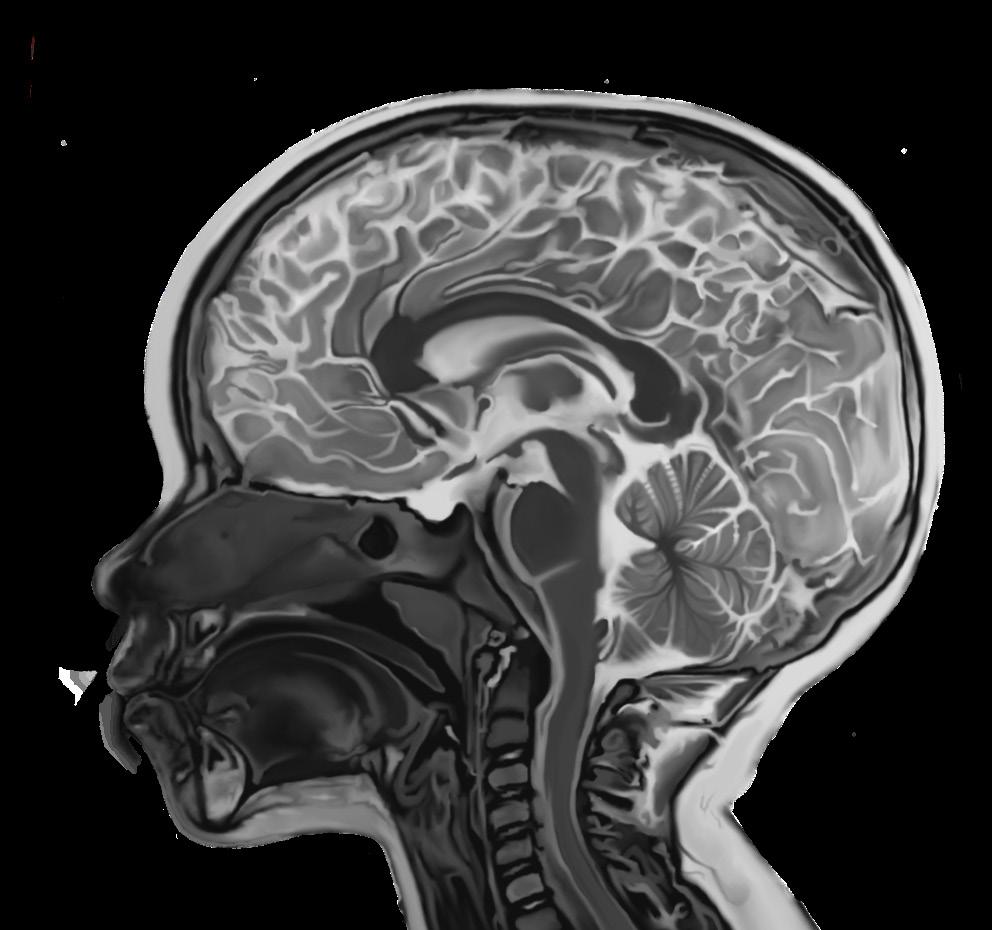

For physicians to detect and diagnose PAM, a thorough patient history must be compiled, identifying recent freshwater exposures and any presentation of CNS symptoms. For a definitive diagnosis, amoebae must be detected in a CSF analysis.2 Other techniques include antigen detection by immunohistochemical staining, polymerase chain reaction, and cultures using CSF or tissue samples.2 Magnetic resonance imaging (MRI) and computed tomography (CT) scans can also be done, but findings may be unremarkable during the critical early stages of infection. In later-stage infection, diffuse haemorrhages or infarctions in the brain’s grey matter may appear in an MRI, while cerebral edema and the destruction of cisterns, enlarged pockets filled with CSF fluid, may be found in CT scans.2,4,12